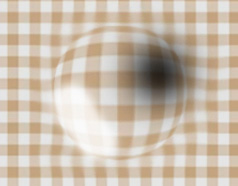

사물이 휘어보인다. 중심시야가 어둡거나 보이지 않는다.

이 부위에 변화가 생기면 중심 시력이 떨어져 글씨가 흐려 보이거나 직선이 휘어져 보이는 증상이 나타나는데, 이를 황반변성이라고 합니다.